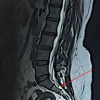

We present the case of a 55-year-old woman with complaints of severe pain localized to the inner aspect of the thigh and gluteal region for the past 6 months. Our patient did have any history of urinary incontinence, constipation, or sexual dysfunction. The patient had a history of hysterectomy done 5 years ago which was uneventful. The patient was put on conservative management elsewhere with pain medications and physiotherapy which did not relieve her symptoms. On examination, the pain was corresponding to S2 and S3 sacral dermatomal levels with loss of sensation and preserved motor functions without any neurological deficit elsewhere. MRI showed a cystic lesion occupying the spinal canal with the size of about 1.3 × 0.7 cm around the S2 vertebra, as shown in Fig. 1.

The cyst appears hypointense on T1 and hyperintense T2-weighted images. Remodeling changes were noted around the canal in computed tomography (CT) imaging of the sacrum, as shown in Fig. 2.